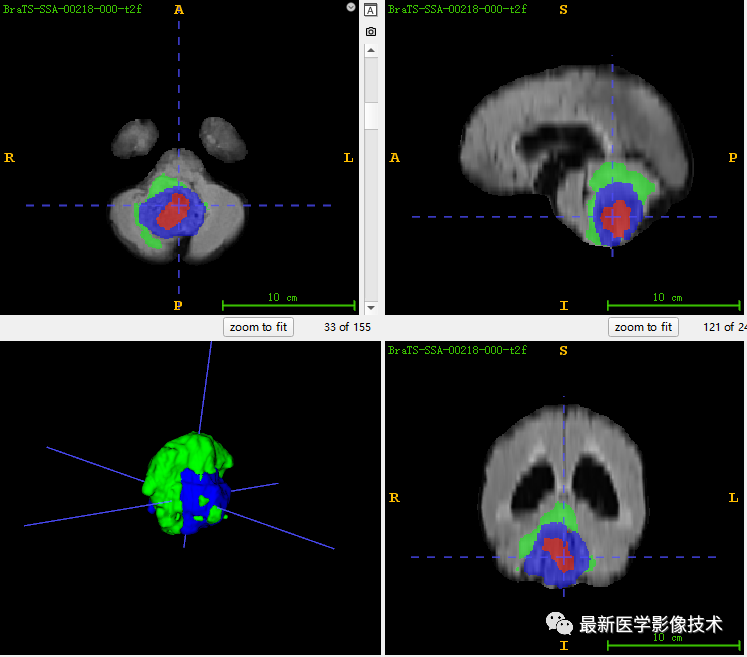

7、测试集分割结果